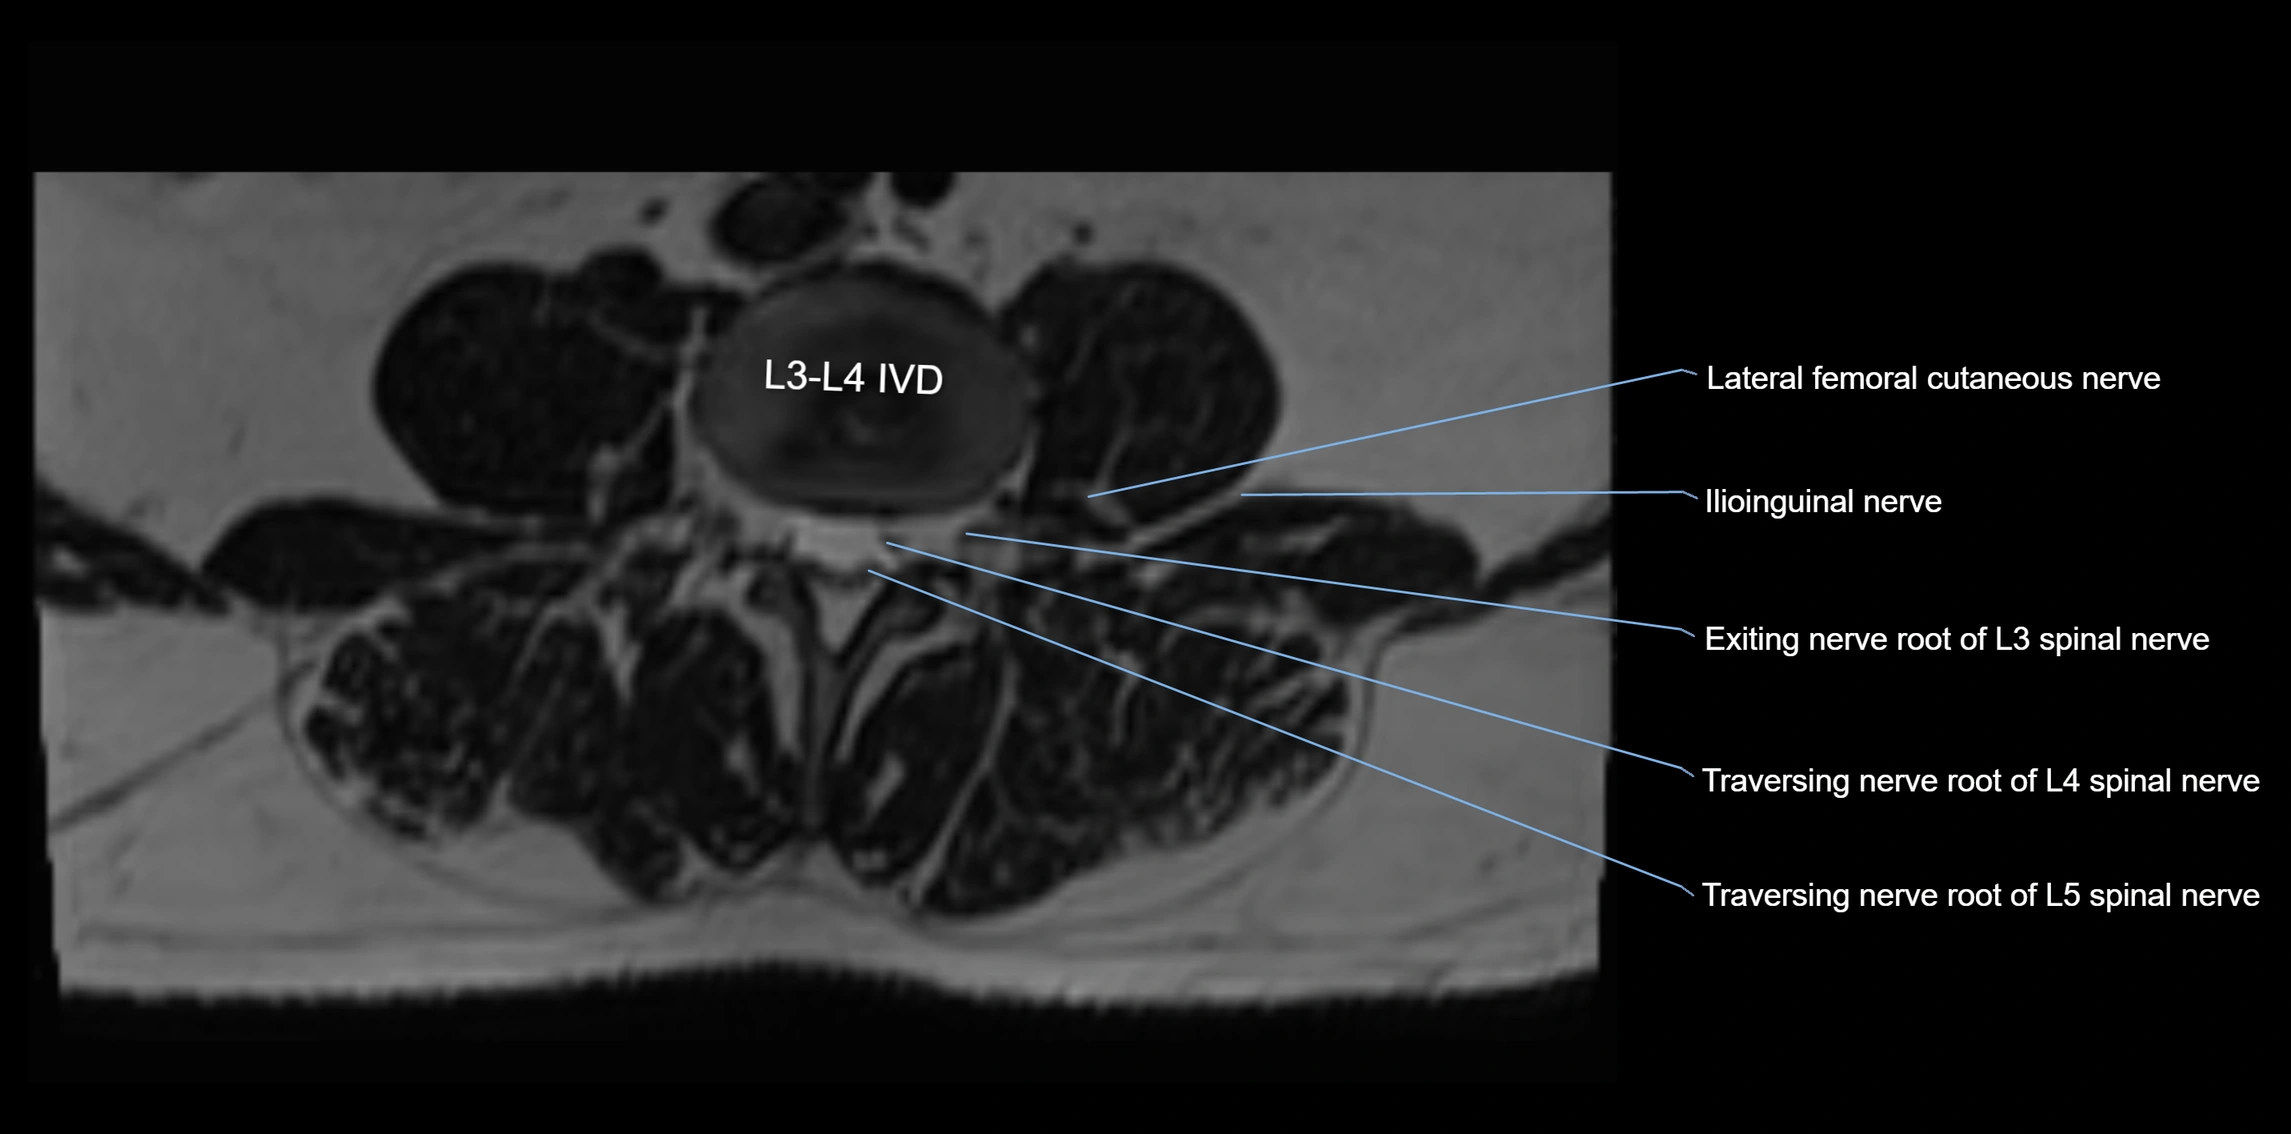

MRI Appearance

T1-weighted images:

• Nerve appears as a very thin low-to-intermediate signal intensity structure

• Surrounded by bright fat, aiding visualization

T2-weighted images:

• Nerve shows intermediate to mildly hyperintense signal compared to muscle

• Pathological involvement appears brighter

STIR (Short Tau Inversion Recovery):

• Normal nerve appears dark

• Inflamed or entrapped nerve appears bright hyperintense

T1 Fat-Sat Post-Contrast:

• Normal nerve enhances minimally

• Pathologic nerve (neuritis, entrapment, tumor infiltration) shows focal or diffuse enhancement

3D T2 SPACE / CISS:

• Nerve appears intermediate to mildly hyperintense compared to muscle

• Surrounded by bright fat or CSF, improving visualization

• Best sequence for mapping small pelvic nerves such as the anococcygeal